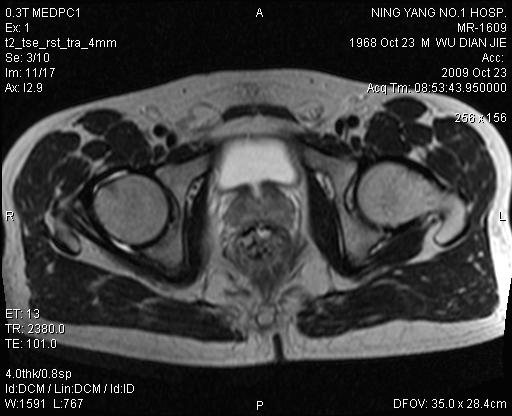

右髋痛一周,渐加重。右髋活动受限

1.右侧股骨头颈交界区滑膜疝2.右侧髋关节少量积液3.右侧髋臼局限异常信号,性质待定,建议定期复查

右侧股骨颈疝窝!

右侧股骨颈疝窝!  右侧髋关节少量积液

右侧股骨颈滑膜疝!  右侧髋关节少量积液